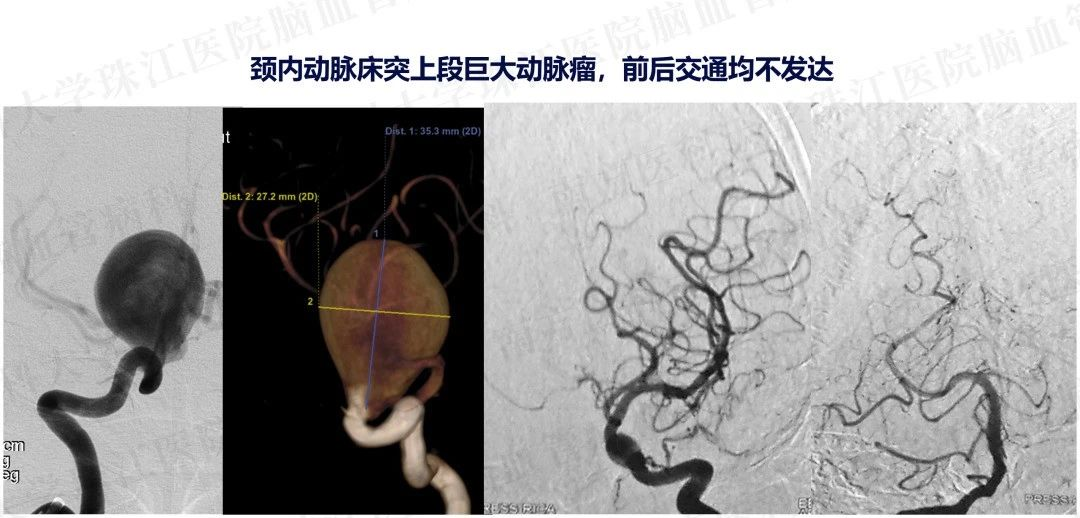

患者入院后造影发现“颈内动脉床突上段巨大动脉瘤,大小约2.7x3.5cm。决定行PIPELINES密网支架植入治疗。

患者入院后造影发现“颈内动脉床突上段巨大动脉瘤,大小约2.7x3.5cm。决定行PIPELINES密网支架植入治疗。